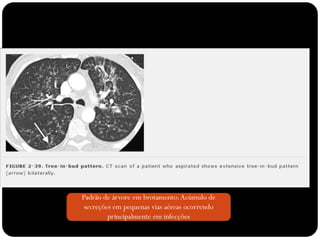

Padrão de árvore em brotamento: Acúmulo de

secreções em pequenas vias aéreas ocorrendo

principalmente em infecções

Sinal de árvore em brotamento

Padrão de árvoreem brotamento: Acúmulo de secreções em pequenas vias aéreas ocorrendo principalmente em infecções